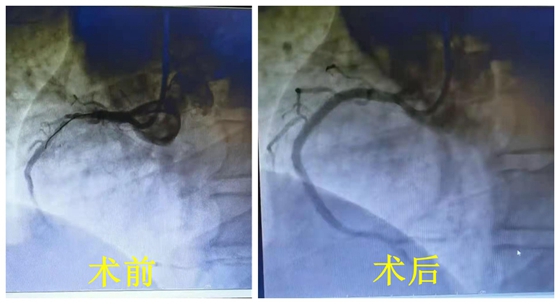

患者术前、后冠脉造影对比图

完善术前准备后,范爱德主任医师、杨国栋副主任医师、龚辉主治医师携手手术团队先进行右冠冠脉造影提示右冠近段弥漫性狭窄50%-99%,中段局限性狭窄80%。随后完善血管内超声检查示:右冠近段弥漫性狭窄伴环形钙化,中段严重狭窄,未见严重钙化,建议近段行金属药物洗脱支架植入,中段行生物可吸收降解支架植入。患者及家属商量后同意手术方案,严格遵循PSP原则以及在血管内超声指导下,顺利植入支架,手术过程顺利,没有出现并发症。